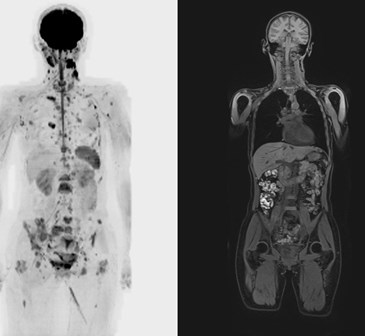

Результат спільної дифузно-зваженої МР-томографії всього тіла - це тривимірне зображення всього тіла, зібране з декількох тисяч знімків. Воно цінно для фахівців з різних галузей медицини, так як дає інформацію про стан усіх органів і тканин людини. Завдяки дифузній МРТ діагностують:

DWI всього тіла

Спеціальне програмне забезпечення (Fusion) дозволяє зіставляти дифузно-зважені зображення (DWI) зі звичайними МР-зображеннями, дозволяючи точно локалізувати патологічний процес.